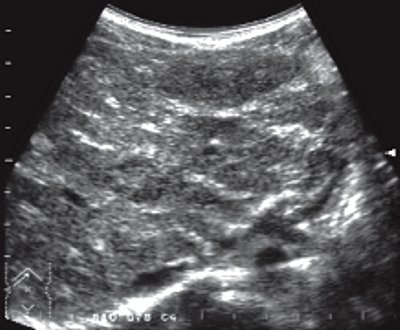

У всех детей с аутоиммунным гепатитом на стадии хронического гепатита наблюдалось диффузное увеличение печени. Четкой зависимости от активности процесса или давности заболевания не прослеживалось. Увеличение правой доли составило в среднем 20%, а левой доли - 8% по верхненижнему и 20% по медиально-латеральному размерам по сравнению с нормальными возрастными показателями. Контур печени был ровный, но с выраженной дольчатостью. Углы долей соответствовали нормальному контуру печени. Отмечалась гиперэхогенность паренхимы. Неоднородность ее была обусловлена гипер- и гипоэхогенными участками сред них размеров (3-5 мм), гиперэхогенной тяжистостью по ходу ветвей воротной вены, что создавало впечатление сетчатости печеночного рисунка (рис. 1 а). Визуализировались единичные печеночные вены с небольшой протяженностью от места впадения в нижнюю подую вену, тонкие, горизонтально направленные, с ровным контуром (косой срез печени). Ослабления ультразвука не наблюдалось, и паренхима печени хорошо прослеживалась до заднего контура. Диаметр ствола воротной вены оставался в пределах допустимых значений. Имела место гиперэхогенность стенок как ствола, так и мелких ветвей воротной вены. У одного ребенка определялось не большое раскрытие пупочной вены (до 2 мм) без признаков кровотока в ней.

а) При хроническом гепатите.

Эхографическая картина паренхимы печени у больных с аутоиммунным гепатитом на стадии хронического гепатита характеризовалась неоднородностью за счет гипер- и гипоэхогенных участков средних размеров, гиперэхогенной тяжистостью по ходу ветвей воротной вены и обеднением сосудистого рисунка. Такая картина отличалась от мелкодиффузной неоднородной паренхимы печени, наблюдаемой при гепатитах В и С в группе сравнения. Различия выявлялись также в характеристике сосудистого русла: обилие печеночных вен с ровным контуром, горизонтально направленных, прослеживающихся по всему срезу паренхимы печени. Не было ярко выраженной гиперэхогенной тяжистости по ходу ветвей воротной вены (рис. 1в), Иногда отмечались параллельные линейные средней эхогенности сигналы по ходу мелких ветвей воротной вены, но, как правило, это сочеталось с увеличением желчного пузыря, его деформациями и снижением сократительной функции. Совокупность этих признаков расценивалась как дискинезия желчевыводящих путей с явлениями холестаза.